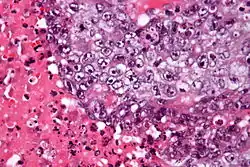

Carcinoma embrionário

Carcinoma embrionário é um tumor de células germinativas maligno raro. Geralmente (84 a 98%) aparece junto a outro tumor de células germinativas (tumor mixto). Pode ser um tipo de câncer de ovário ou um tipo de câncer de testículo. É mais comum em adultos, por volta dos 30 anos de idade. Na maioria dos casos só é diagnóstico tardiamente, com metástases.[1]